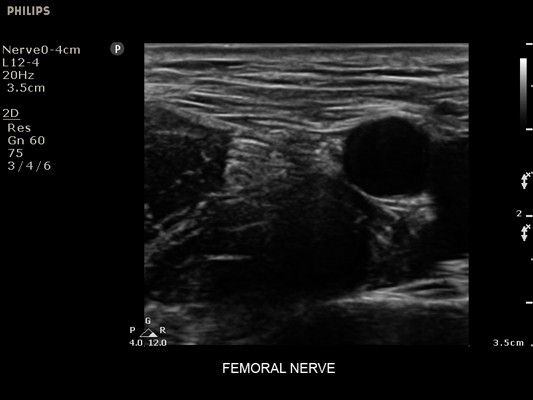

• Усиленная визуализация иглы без потери качества изображения окружающих тканей

• Метки центральной линии на датчиках L12-4 и C6-2 для упрощения внеплоскостной навигации

• Сосудистый доступ

• Диагностика нервов

• Линейный УЗИ датчик Philips L12-4